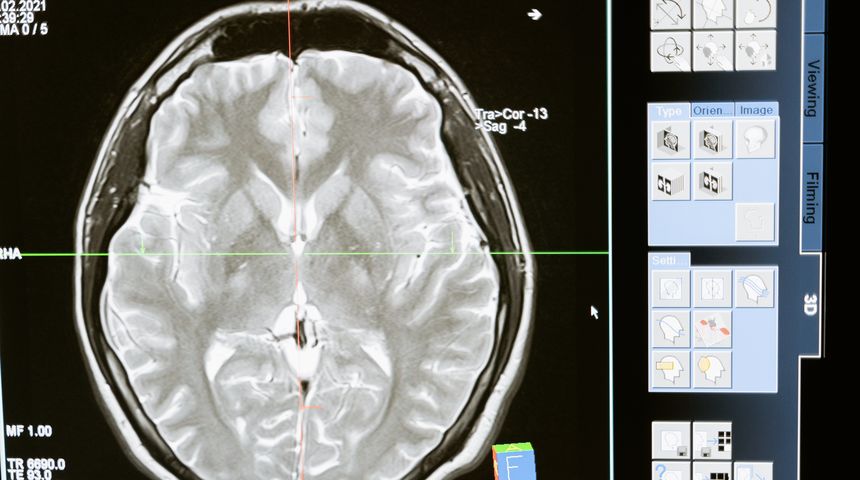

“Tijekom niza magnetskih rezonanci gledao sam kako tumor

potpuno nestaje”, rekao je Grill za AFP.